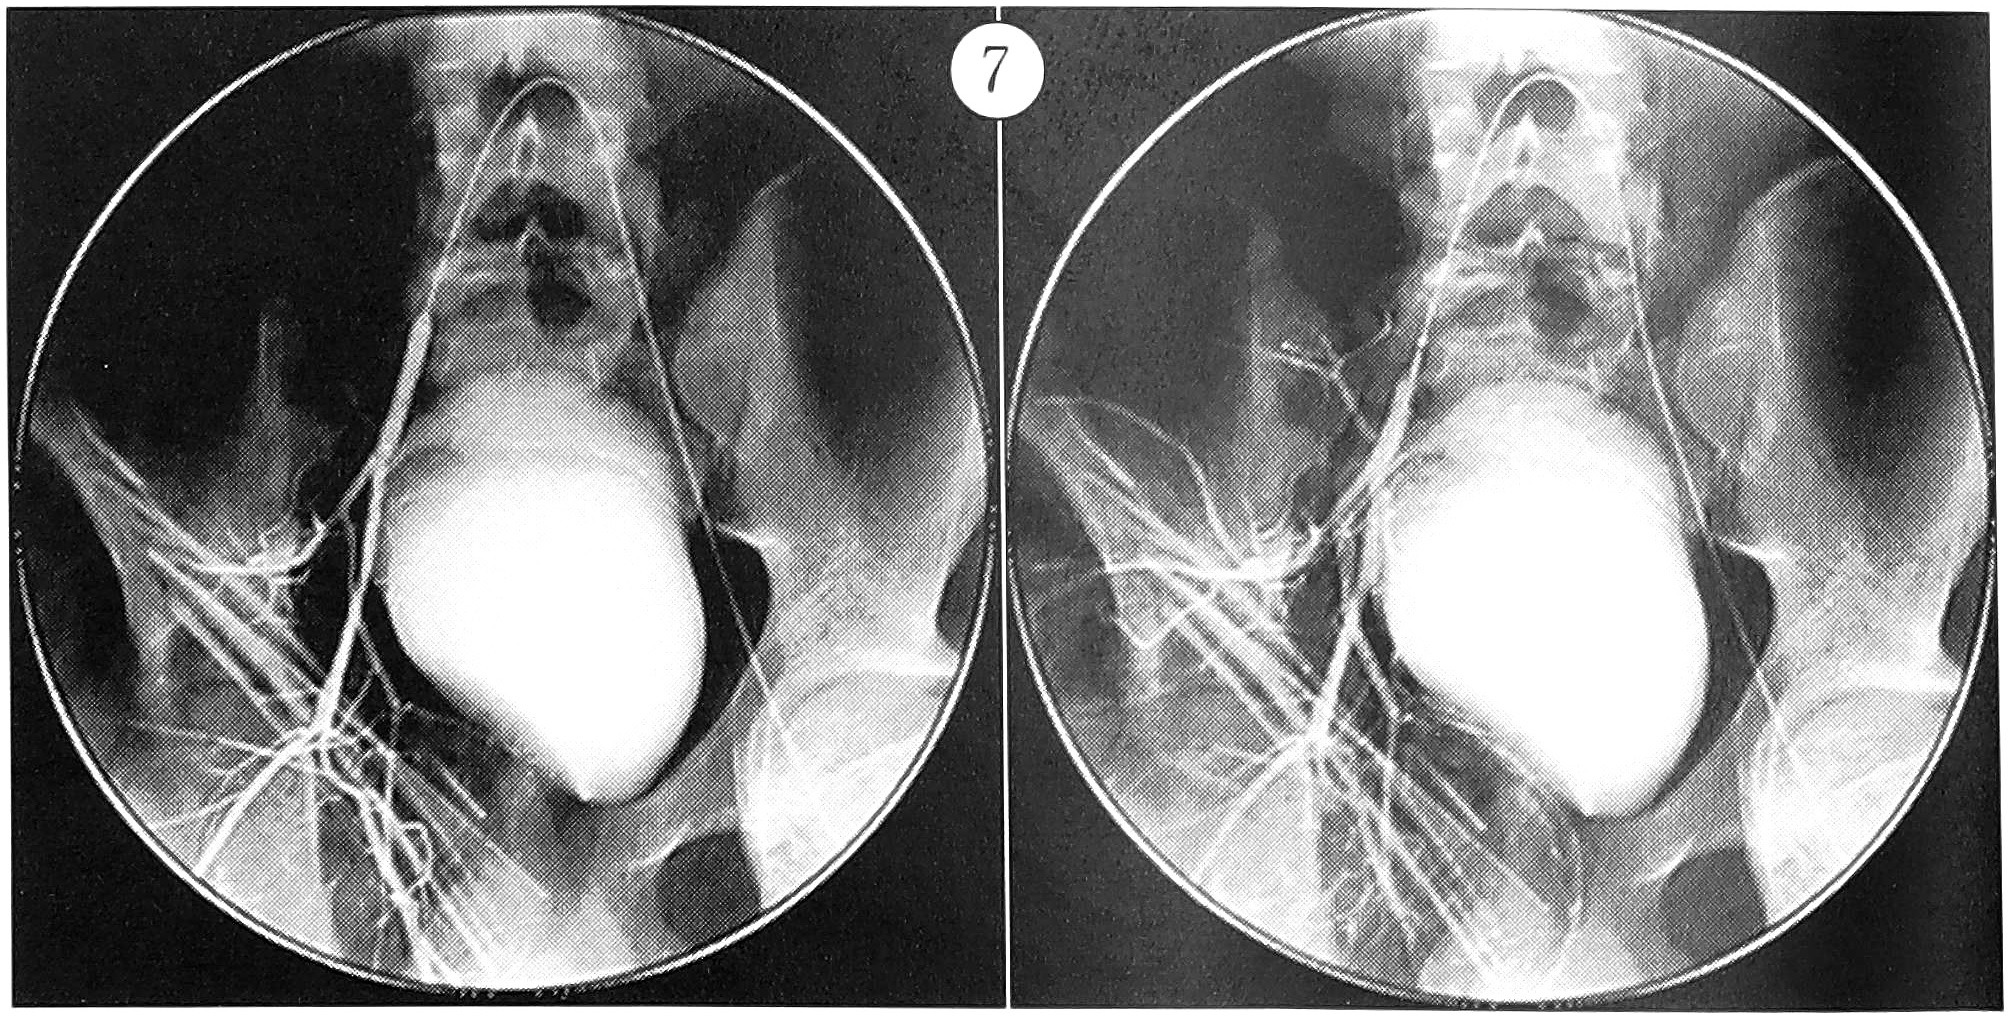

Операция выполнялась под эндотрахеальным наркозом. Доступом по гребню подвздошной кости до лонного сочленения выделен сосудисто-нервный пучок, обнажено патологическое образование синюшного цвета, которое пульсировало в области вертлужной впадины и верхней ветви лонной кости. Произведена экскохлеация оболочек кисты в области вертлужной впадины и лонной кости. Ацетабулярная хрящевая пластинка местами была перфорирована. Смоделирован каркас верхней ветви лонной кости и дна вертлужной впадины с помощью массивных поверхностно-деминерализованных перфорированных трансплантатов «перфоост». По окончании оперативного вмешательства баллонный катетер спущен, кровотечения в ране не отмечалось. Через ангиографический катетер произведен контроль правой подвздошной артерии (рис. 7).

Рис. 7. Баллонный катетер спущен, кровоток по внутренней подвздошной артерии сохранен.